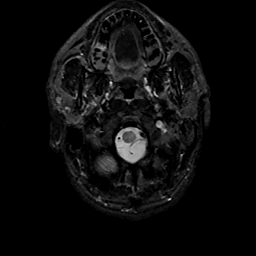

MR Study #11, May 5, 1991 -- Slice #2